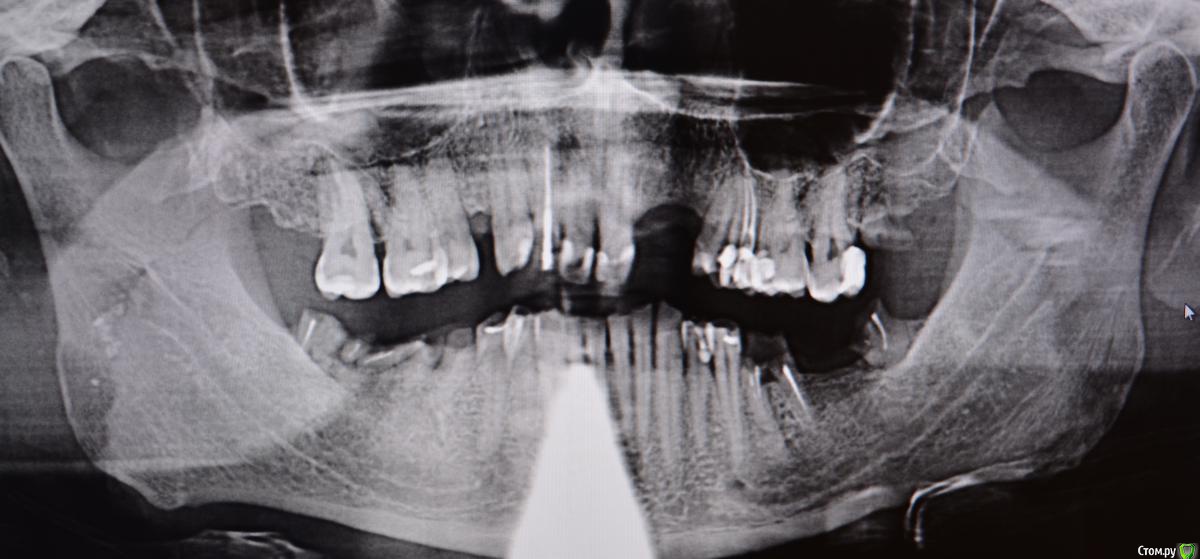

alekcandr ovs. Опубликовано 9 января, 2018 Поделиться Опубликовано 9 января, 2018 Пациент 43 года, очень боялся стоматологов и доболтаться до такого, с чего начать ???Мой предварительный план лечения депрограмация ,регистрация Ц.С, поднятие прикуса , Wax up ,хир.удлинение 1.1,1.6,1.7,2.1,2.4,2.5,2.6,2.7,имплантация 3,4 сегмент, тотал В.Ч, Н.Ч мостовидные протезы 1.5--1.3----1.1 2.1-------2.4,2.5.может искус.десна фронт !!!! 1. Вопрос чем лучше депрограмировать и найти Ц.С ????2.На сколь максимум можно удлинять моляры В.Ч ограничитель трифуркация ??? 3. Коллеги помогите сложный для меня случай!!! Всем добра Ссылка на комментарий